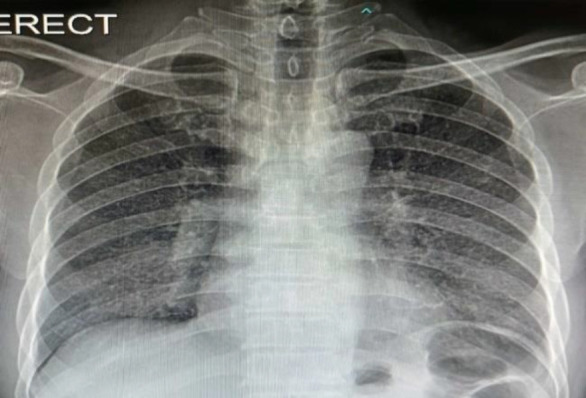

Introduction: Tuberculosis (TB) is an important contagious disease and a major public health problem globally. It may manifest as pulmonary TB or primary or secondary extrapulmonary TB. Primary oropharyngeal TB is very rare and may mimic presentation of oropharyngeal malignancy especially in the negative initial TB workup.

Case report: We would like to highlight a case of an elderly man presented with ipsilateral oropharyngeal mass and cervical lymph node (LN) enlargement, mimicking oropharyngeal malignancy with regional LN metastasis.